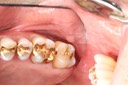

Photos of Clinical Operations

Drs. Peter Kearney, Terry McKay, John St. Germain, and Laurie Vanzella - Mentors